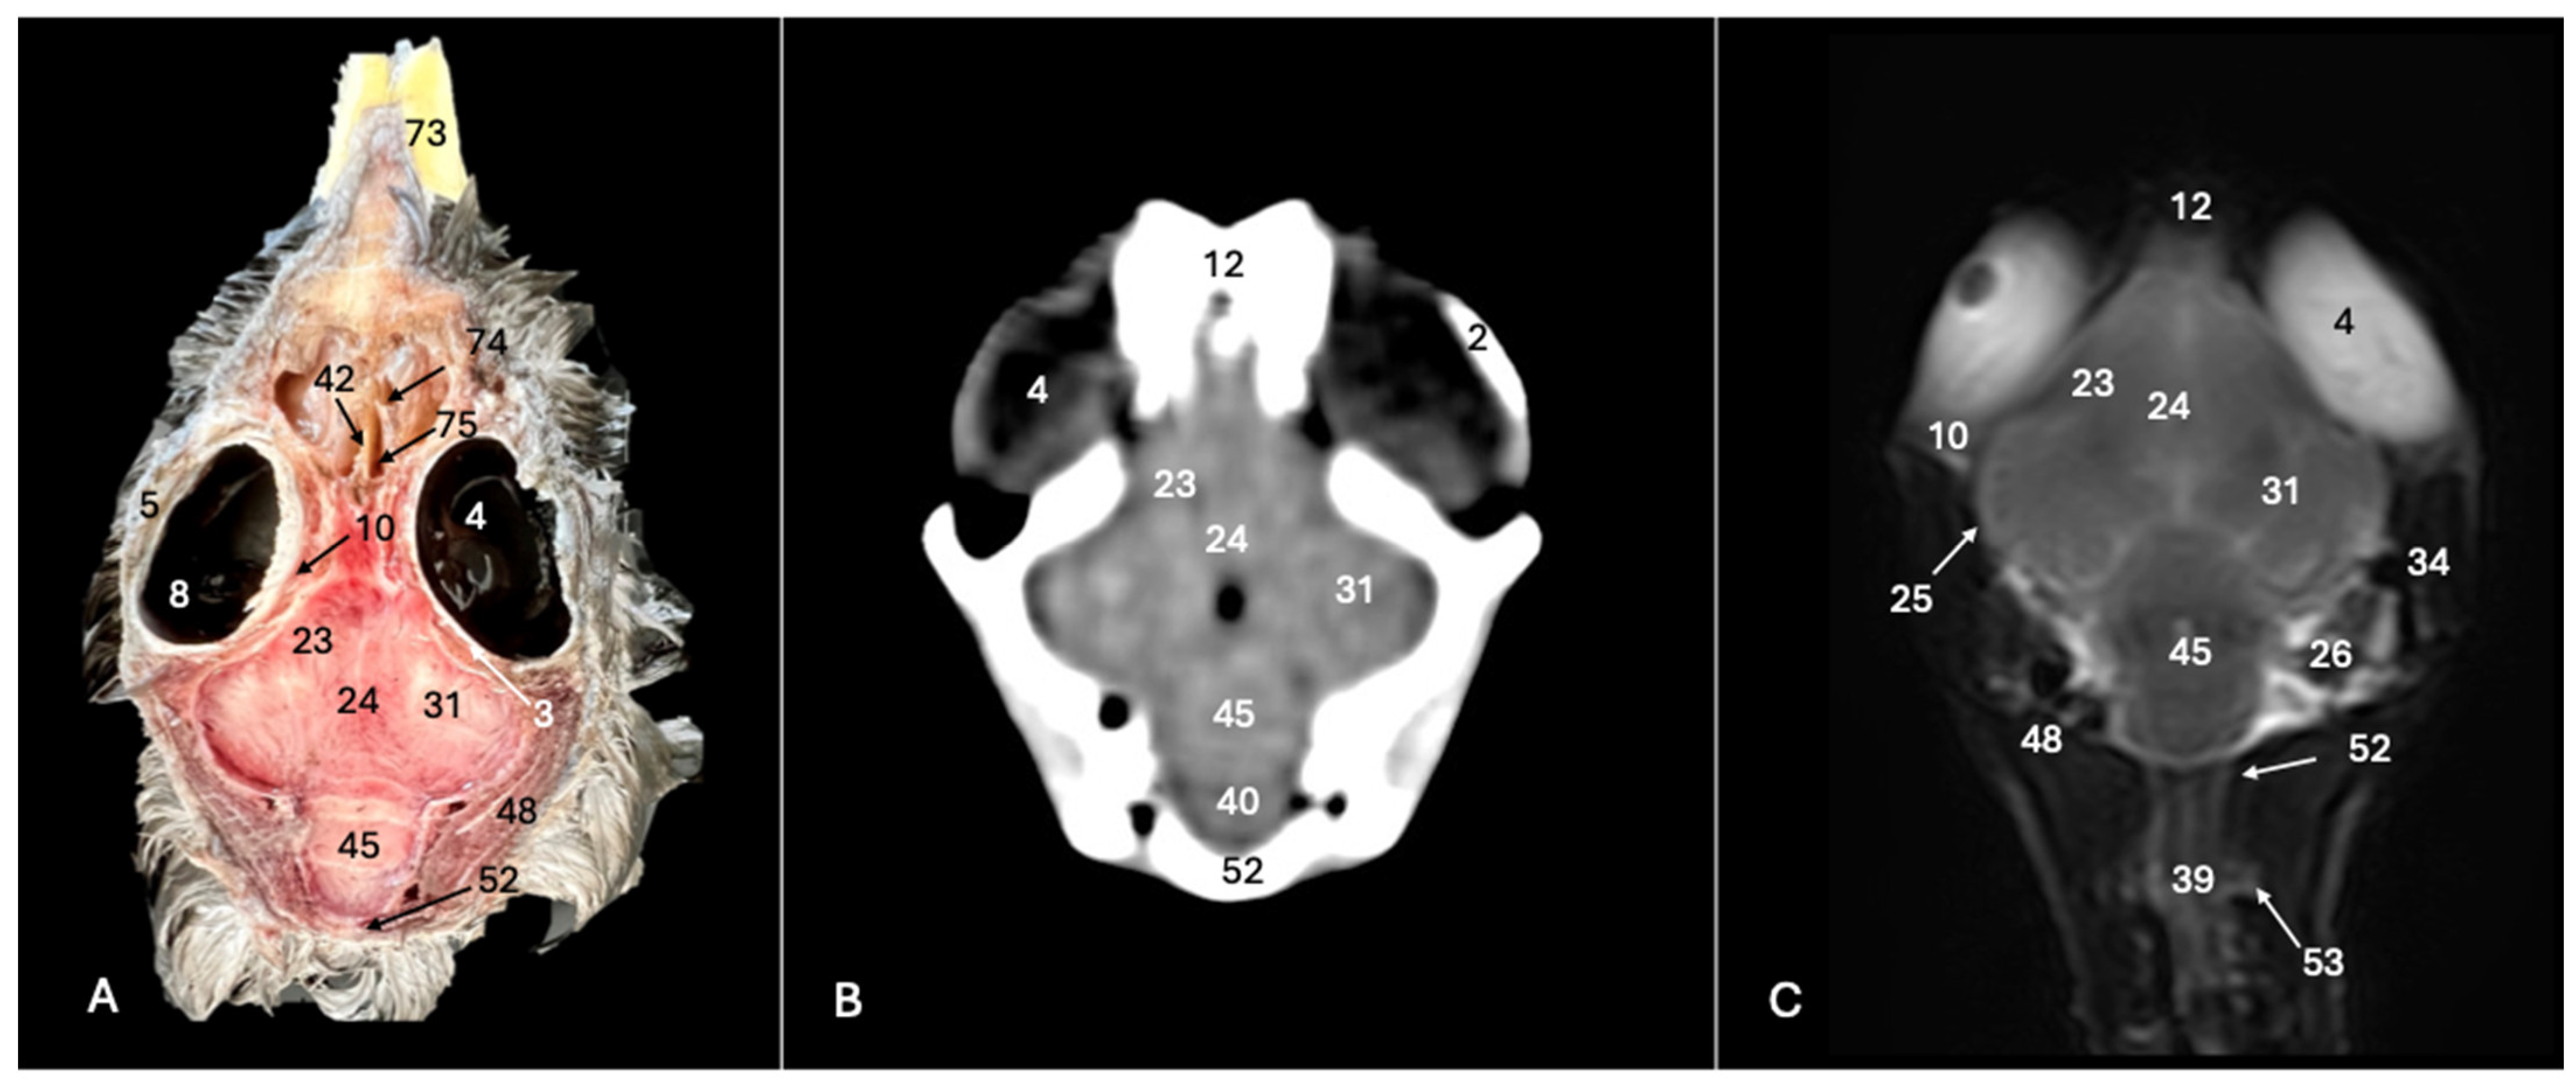

Figure 4. Anatomical cross-section (A), soft tissue CT window (B) and T2-weighted MR (C) transverse images of the Cory’s shearwater head at the level of the optical lobes, corresponding to line III in Figure 1. 14: Mandible; 16: cerebral hemisphere; 17: trachea; 18: tracheal ring; 19: musculus pterygoideus pars ventralis. 20: musculus tracheolateralis; 21: hyperpallium; 22: 3rd ventricle; 24: fissura longitudinalis cerebri; 25: meninges; 26: middle ear; 27: tympanic bulla; 28: basioccipital bone; 31: optical lobe; 32: os parietale; 34: external acoustic canal; 35: inner ear; 44: otic bone; 68: cricoid cartilage; 69: interparietal bone; 78: tentorial process.

Figure 8. Anatomical cross-section (A), soft tissue CT window (B) and T2-weighted MR (C) dorsal images of the Cory’s shearwater head at the level of the ventral cerebral hemisphere, corresponding to line VII in Figure 1. 2: Sclerotic ossification; 3: sclera; 4: camera vitrea bulbi; 5: cornea; 8: retina; 10: extraocular muscles; 12: os frontale; 23: vallecula telencephali; 24: fissura longitudinalis cerebri; 25: meninges; 26: middle ear; 31: optical lobe; 34: external acoustic canal; 39: medulla spinalis; 40: medulla oblongata; 42: nasal septum; 45: cerebellum (body); 48: musculus constrictor colli; 52: os supraoccipitali; 53: cervical vertebra; 73: beak; 74: concha nasalis media; 75: concha nasalis caudalis.